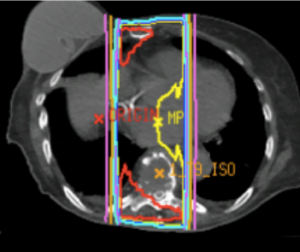

Oncological assessment is centred around the degree of response to potential treatment such as cEBRT, SRS, surgery, chemotherapy, hormonal, targeted or immunotherapeutic agents. Currently radiation is the mainstay of spinal metastasis and therefore the primary consideration. On the basis of expected response to cEBRT tumours may be considered radiosensitive (such as lymphoma, breast or prostate) or radio resistant (such as sarcoma, melanoma, lung (Oncological assessment is centred around the degree of response to potential treatment such as cEBRT, SRS, surgery, chemotherapy, hormonal, targeted or immunotherapeutic agents. Currently radiation is the mainstay of spinal metastasis and therefore the primary consideration. On the basis of expected response to cEBRT tumours may be considered radiosensitive (such as lymphoma, breast or prostate) or radio resistant (such as sarcoma, melanoma, lung (NSCLS) and renal cell). The game has changed with the advent of SRS for these tumours with durable local control in patients with oligometastatic tumours treated with 24Gy regardless of tumour histology. The efficacy of high dose SRS for local control has reduced the need for extensive surgical resections with resultant morbidity. The game has changed with the advent of SRS for these tumours with durable local control in patients with oligometastatic tumours treated with 24Gy regardless of tumour histology. The efficacy of high dose SRS for local control has reduced the need for extensive surgical resections with resultant morbidity.